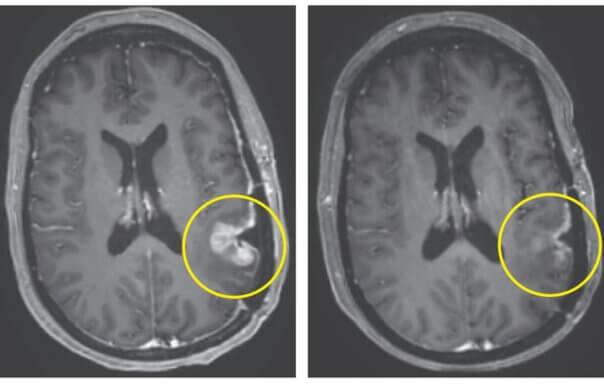

π±ΠΠ»Π°Π³ΠΎΠ΄Π°ΡΡ Π½ΠΎΠ²ΠΎΠΌΡ ΡΠΏΠΎΡΠΎΠ±Ρ ΡΠ΅ΡΠ°ΠΏΠΈΠΈ ΠΎΠΏΡΡ ΠΎΠ»Ρ ΠΌΠΎΠΆΠ΅Ρ ΠΈΡΡΠ΅Π·Π½ΡΡΡ Π·Π° 5 Π΄Π½Π΅ΠΉ

Π§Π΅ΡΠ΅Π· Π½Π΅ΡΠΊΠΎΠ»ΡΠΊΠΎ Π΄Π½Π΅ΠΉ ΠΏΠΎΡΠ»Π΅ ΠΎΠ΄Π½ΠΎΠΊΡΠ°ΡΠ½ΠΎΠ³ΠΎ Π»Π΅ΡΠ΅Π½ΠΈΡ Ρ Π±ΠΎΠ»ΡΠ½ΡΡ Π½Π°Π±Π»ΡΠ΄Π°Π»ΠΎΡΡ Π·Π½Π°ΡΠΈΡΠ΅Π»ΡΠ½ΠΎΠ΅ ΡΠΌΠ΅Π½ΡΡΠ΅Π½ΠΈΠ΅ ΡΠ°Π·ΠΌΠ΅ΡΠΎΠ² ΠΎΠΏΡΡ ΠΎΠ»Π΅ΠΉ, Π° Ρ ΠΎΠ΄Π½ΠΎΠ³ΠΎ ΠΏΠ°ΡΠΈΠ΅Π½ΡΠ° Π² ΡΠ΅ΡΠ΅Π½ΠΈΠ΅ 5 Π΄Π½Π΅ΠΉ Π±ΡΠ»Π° Π΄ΠΎΡΡΠΈΠ³Π½ΡΡΠ° ΠΏΠΎΡΡΠΈ ΠΏΠΎΠ»Π½Π°Ρ ΡΠ΅Π³ΡΠ΅ΡΡΠΈΡ.